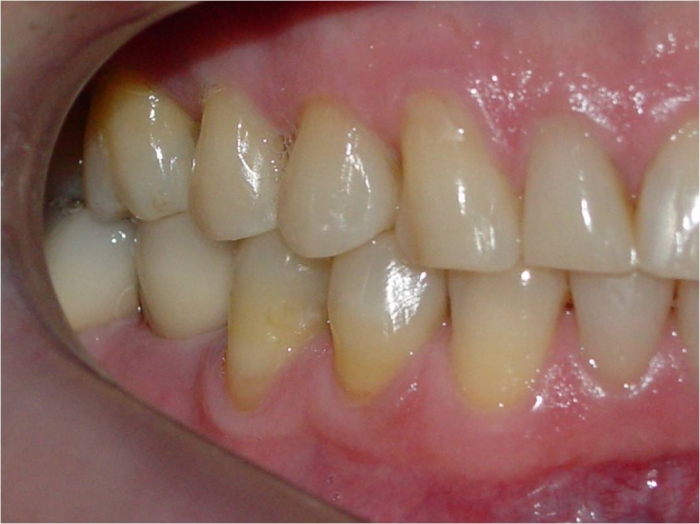

Mordida, após 2 anos da cirurgia